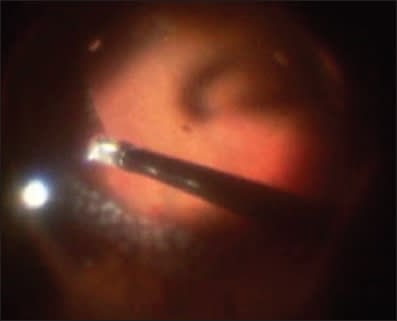

Figure 4. A retinal tear edge can be seen in white, and it has been pushed posteriorly by air.

During the Perfluoron-air exchange, there is a greater chance that the edge of a giant retinal tear, retinotomy, or retinectomy may slip posteriorly than during a Perfluoron�silicone oil exchange (Figure 4). The force acting on the edge of the retinal defect as the air-BSS interface passes over it is generated primarily by the surface tension of BSS in air, which is approximately 60 dyne/cm (600 μN/cm).11 This is much greater than the force acting on the edge of the retinal defect as silicone oil-BSS interface passes over it. This force is generated primarily by the interfacial tension of silicone oil in BSS, which is approximately 33 dyne/cm (330 μN/cm).11